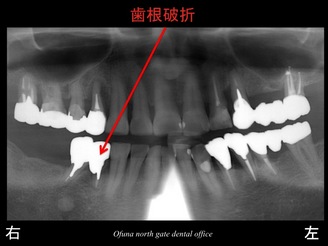

それでは 早速 症例のレントゲンを見ましょう。

以下が初診時のレントゲンです。

『下顎右側の奥歯が欠損しており、噛めない!』

『上顎右側の奥歯がグラグラしている!』

との問題で来院されました。

右下の奥は2歯分欠損していました。

右上もグラグラです。

歯根破折 です。

下顎の右側の1歯が歯根破折 していたのです。

やはり神経のない歯は脆いです。